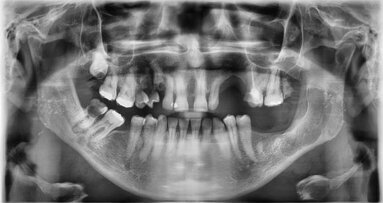

W ocenie radiologicznej zaobserwowano zwiększoną gęstość tkanki kostnej w przypadku użycia PRF do augmentacji zębodołów poekstrakcyjnych.